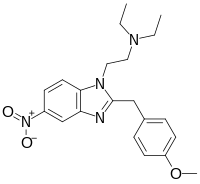

Benzimidazoles

Structures

| Benzimidazoles | ||||

|---|---|---|---|---|

|

|

|

|

|